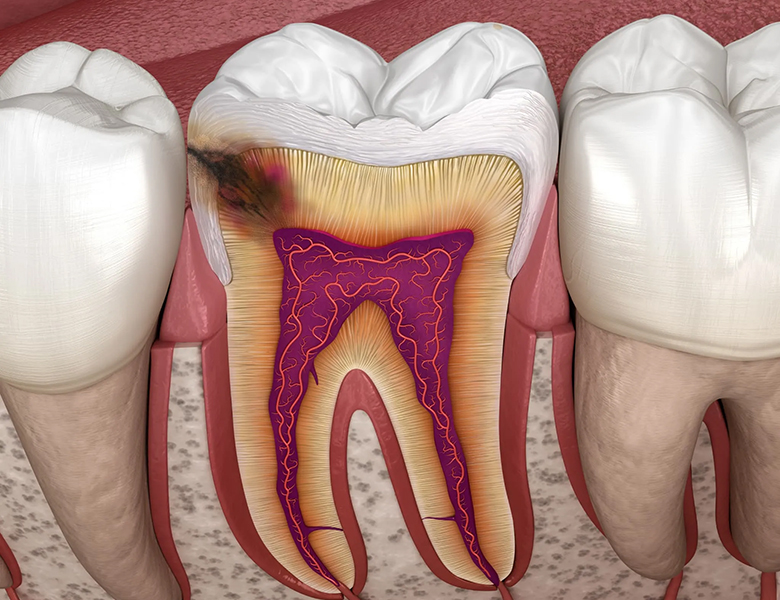

「肉眼」と「マイクロスコープ」の視野の差

歯科治療において「見える」ということは、そのまま「治療の質」に直結します。

裸眼で見ている世界(1倍)

お口の中は暗く、特に奥歯の根の中などは肉眼ではほとんど見えません。

多くの歯科治療は、手先の感覚やレントゲン写真から推測する「経験と勘」に頼らざるを得ないのが現状です。

マイクロスコープで見ている世界(最大20倍以上)

肉眼の約20倍の世界では、歯の表面にある目に見えない小さな亀裂、古い詰め物のわずかな段差、複雑に枝分かれした根管(歯の神経の通り道)の隅々までが、まるで明るい昼間に映画のスクリーンを見ているかのように鮮明に映し出されます。

根管治療(歯の神経の治療)

歯の根の中(根管)は、暗く、非常に細く、複雑に枝分かれしています。

肉眼でこの中を覗くことは、暗いトンネルの奥を外から眺めるようなものです。

「隠れた管」の発見

多くの歯科医師が肉眼で見落としてしまう「第4根管」と呼ばれる微細な神経の通り道。

これを見落としたまま蓋をすると、数年後に必ずと言っていいほど再発します。

マイクロスコープは最大20倍以上の拡大と直下への強い光により、この隠れた原因を特定します。

破折(ヒビ)の早期発見

「根の治療をしても痛みが引かない」原因の多くは、肉眼では見えない微細なヒビです。

これを見逃して治療を続けることは、底の割れたコップに水を注ぐようなもの。

マイクロスコープでヒビを早期に発見することで、無駄な治療を避け、適切な処置方針を立てることができます。

歯髄保存治療(神経を残すための処置)

1ミリ以下の精密な除去

マイクロスコープを使用すれば、虫歯に侵された組織と、温存できる健康な組織の境界が鮮明に見えます。

健康な部分を1ミリも無駄にせず、感染部位だけを精密に除去することで、従来は諦めていた神経を残せる可能性が飛躍的に高まります。